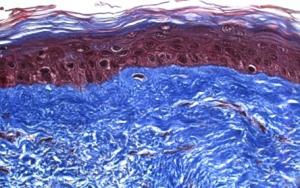

Cette recherche de l’Université de Laval, présentée dans la revue Advances in Skin and Wound Care propose l’utilisation de pansements de peau humaine pour soigner les ulcères cutanés, en particulier, ceux réfractaires aux traitements courants. Il s’agit de dispositifs de pansements constitués de substituts de peau cultivés in vitro. Ils montrent ici leur efficacité chez des patients atteints d’ulcères veineux de jambe, qui ne parviennent pas à cicatriser.

Le traitement usuel des ulcères comprend le nettoyage de la plaie, le recours à certains dispositifs de pansements et à la compression. Alors que l’autogreffe cutanée, une autre option thérapeutique,implique le prélèvement de peau sur d’autres surfaces du corps, les chercheurs de Laval ont eu l’idée de cultiver de la peau in vitro pour créer des pansements cutanés sans aucun biomatériau. Le prélèvement de peau du patient, nécessaire au processus defabrication, est très limité, d’ 1 cm2 seulement. Les cellules extraites sont ensuite cultivées in vitro, durant 8 semaines, pour fabriquer ce substitut cutané. Le pansement cutané est ensuite déposé sur l’ulcère comme un pansement et remplacé, si nécessaire, chaque semaine. C’est à la fois une barrière physique mais également un pansement cicatrisant.

Des tests concluants sur 5 patients : Avec ce nouveau dispositif en peau humaine, seules 7 semaines en moyenne ont été nécessaires pour venir à bout de 14 ulcères anciens de 6 mois. Les chercheurs envisagent de tester également ce pansement bio pour le soin des brûlures.

Sources: Communiqué Université de Laval et Advances in Skin and Wound Care doi: 10.1097/01.ASW.0000433102.48268.2a September 2013Prospective Study on the Treatment of Lower-Extremity Chronic Venous and Mixed Ulcers Using Tissue-Engineered Skin Substitute Made by the Self-assembly Approach(Visuel@ LOEX “La peau fabriquée par les chercheurs du LOEX contient un épiderme (en rouge) et un derme (en bleu). Elle sécrète des molécules qui activent les mécanismes naturels de guérison des ulcères »).